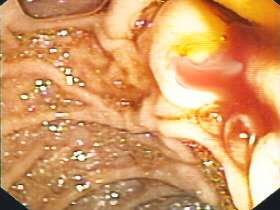

A 40-year-old male patient went to his local A&E department with a short history of feeling unwell and passing black stools. He had a past history of chronic pancreatitis that was attributable to alcohol and a bleeding peptic ulcer some 15 years earlier. He was not taking any medication. On admission, the patient was pale with a heart rate of 75 BPM and his blood pressure was 125/80 mm Hg. The patient’s Hb level was 36 g/L, with a mean corpuscular volume of 8.93, iron 1.253 mmol/L and ferritin 0.27 pmol/L. On endoscopy, the oesophagus and stomach were unremarkable and the photographs show the appearance of the duodenal ampulla (figure 1a–c).

Figure 1a-c | The endoscopic appearance of the duodenal ampulla.

If you look more carefully at the photograph you can see blood trailing away below the bile. This patient has haemobilia.